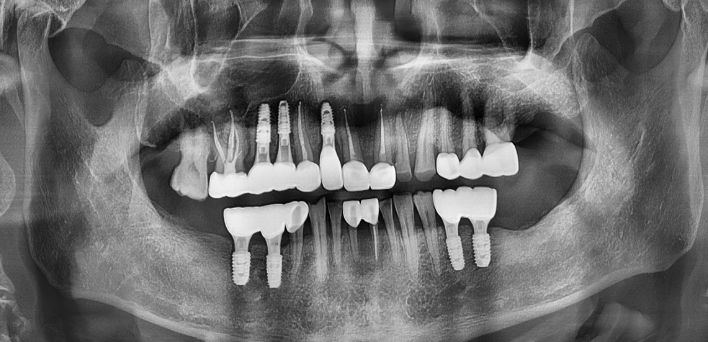

임플란트 : 손 ** 님 (50대)

Before Before

2020.02.30

After After

※ 더서울치과의원은 의료법을 준수하며 위 케이스는 실제 환자의 동의를 얻은 사례로 치료 전, 후가 동일한 환경에서 촬영되었습니다.

환자 케이스에 따라 부작용이 발생할 수 있습니다. 이 부분은 의료진의 충분한 상담과 체크를 통해 예방하고 줄일 수 있습니다.

[임플란트 부작용] 수술 후 관리가 소홀할 경우 출혈, 주위염 등의 부작용이 발생할 수 있어 구강 위생을 철저히 유지하고, 정기적인 검진을 통해 상태를 점검하는 것이 중요합니다.

환자 특징

환자 특징01무치악 상태

환자 특징02수년간 무치악으로 지내심

임플란트가 불가능할것이라

생각하고 내원

위, 아래 6개씩 식립

디지털 풀아치 임플란트